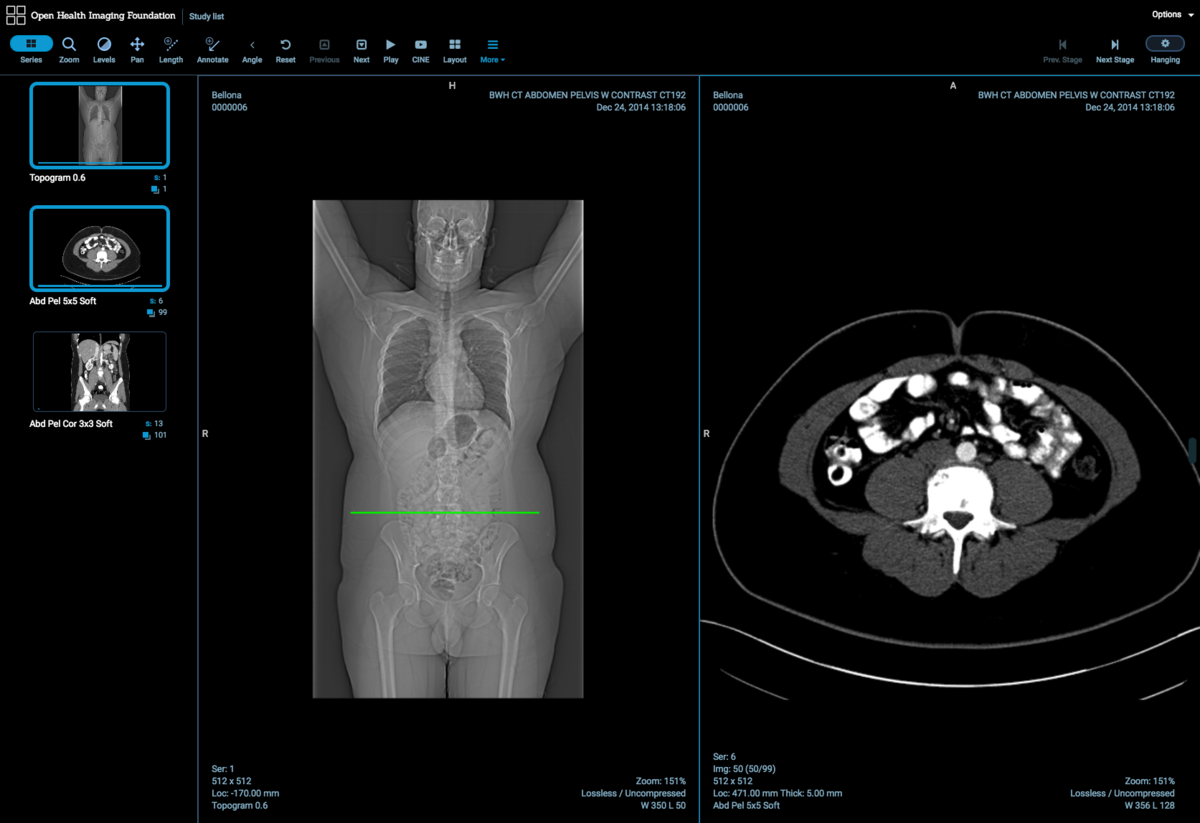

Лазерная камера сетевая для печати изображений на пленке стандарт dicom